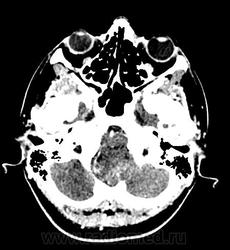

Девушка 30 лет. Поступила с диагнозом Эпилепсия. Неоднократные синкопы, начавшиеся после родов. Роды в начале марта, все благополучно. После родов, как-то так плохо все,шатает, голова болит. Через месяц обратилась в республиканскую больницу, выполнена кт- смешання гидроцефалия. Пролечили и выписали с диагнозом Дистония. Как-то так.

-признаки интравентрикулярной окклюзи выходных отверстий 4 желудочка, с резким расширением всех отдела желудочковой системы.

-резкое сужение охватвающей и большой цистерн

-выраженное расширение хиазмальной и предпонтийной цистерн

-межполушарная,латеральные щели и субарахноидальные пространства значительно уменьшены в объеме за счет увелиения желудочков и отека мозга

-истонены кости основания черепа,усилен рельеф внутренних костных пластин,углублено и расширено турецкое седло,опускание СЧЯ

-ствол и продолговатый мозг в дорсальном отделе уплощены,смещены вентрально

-в полости 4 желудочка объемное образование с учсатками кровоизлияния, с распространением каудально, признаки вклинения миндалин в БЗО,большая цистерна и САП кранио-вертебрального перехода не прослеживаются.

и добавлю,что это было за месяц до "нашей с ней встречи",тогда на кт в респусликанской б-це... кровушка лишь добавилась...